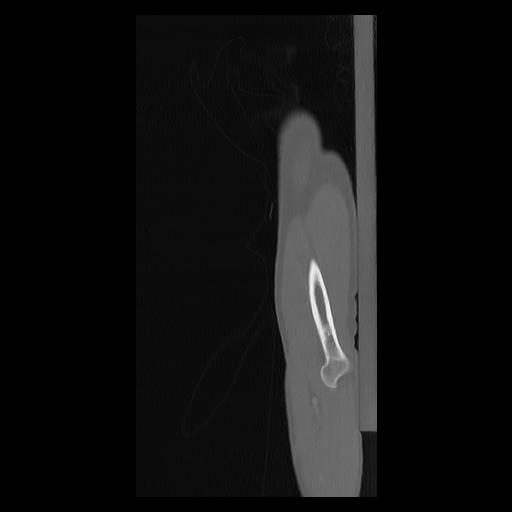

33 PULMON,CE,Sagittal,3.000,PULMON,Sagittal,